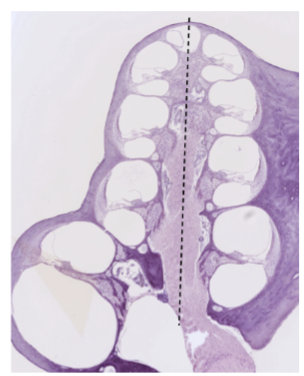

Bilden ovan visar ett tvärsnitt av cochlean med helicotrema upp. Tänk dig att du rör dig från centrum av cochlean (streckade linjen) och ut mot sidan (höger eller vänster): I vilken ordning möter du då nedan celler/strukturer? (1p för alla rätt)

 Hjälp Börja närmast centrum axonbuntar ganglier stria vascularis pelarcell inre hårcell